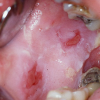

– Üle poolte haigusjuhtudest algab suus esinevate, kiiresti purunevate villidega. Villid on läbipaistvad ja pehmed ning piirduvad algul, mõne kuu jooksul, ainult ühe piirkonnaga ja levivad seejärel üle kogu naha....